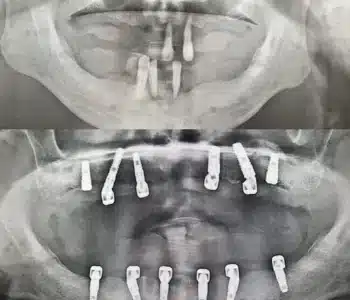

Dr. Seden Aksu is a specialist in modern implantology and surgical dentistry with extensive experience in the management of complex clinical cases. In her practice, she applies comprehensive surgical planning, minimally invasive techniques, and advanced regenerative technologies aimed at restoring both the function of the dentoalveolar system and the aesthetics of the smile. Dr. Aksu has significant experience in performing implant procedures, bone augmentation, and periodontal surgery, including the treatment of patients with severe bone loss. The primary goal of her work is to achieve stable, long-term outcomes in implant rehabilitation and the restoration of oral tissue health.